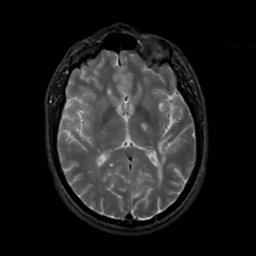

MR Study #6, March 17, 1991 -- Slice #26